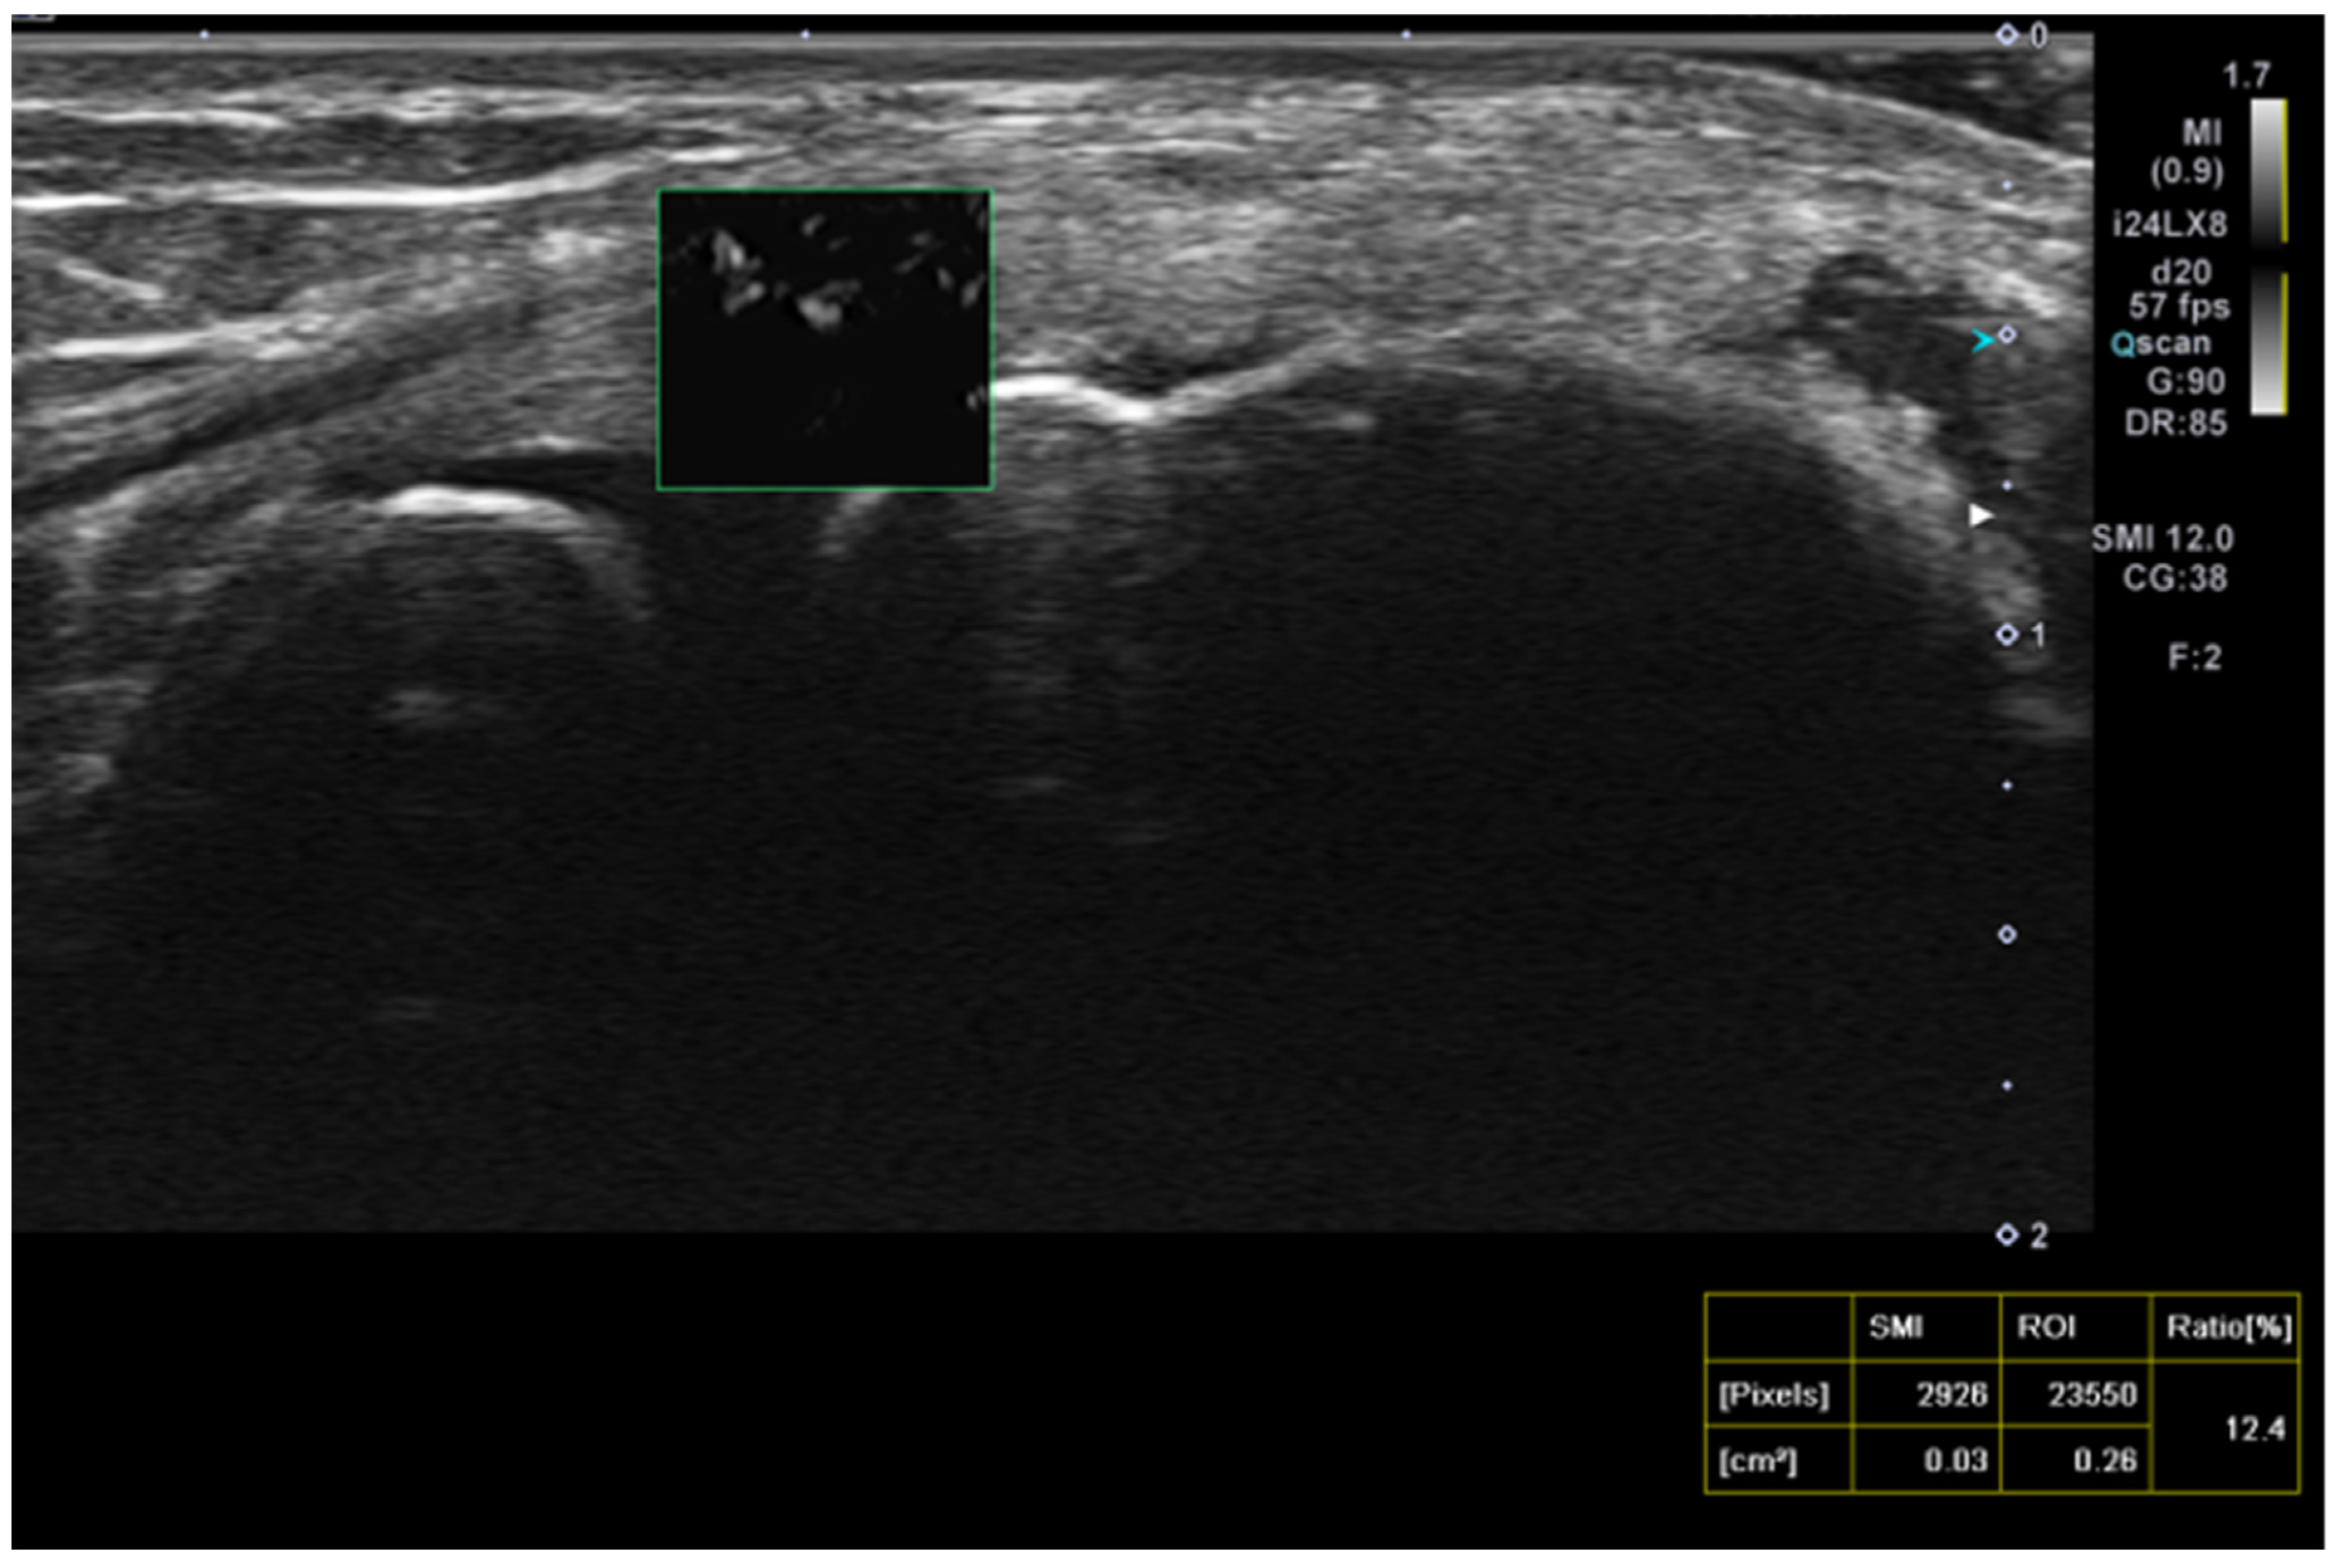

| SMI at baseline | 9.8 | 9.3 | 9.3 | 7.5 | 12.4 | 6.9 | 0.6 |

| SMI after treatment | 9.8 | 7.8 | 10.2 | 8.4 | 7.06 | 6.6 | 0.2 |